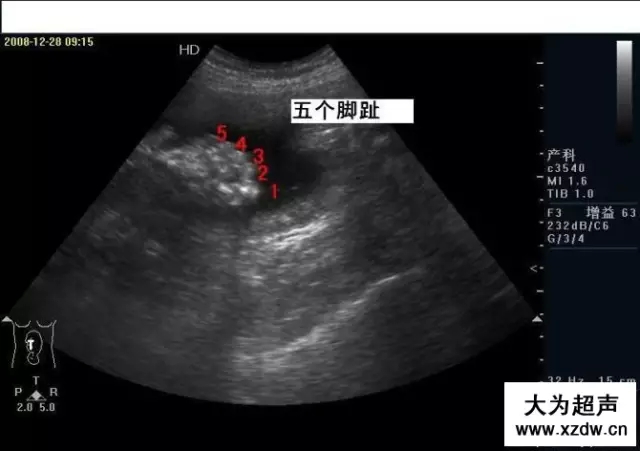

產科超聲正常圖片